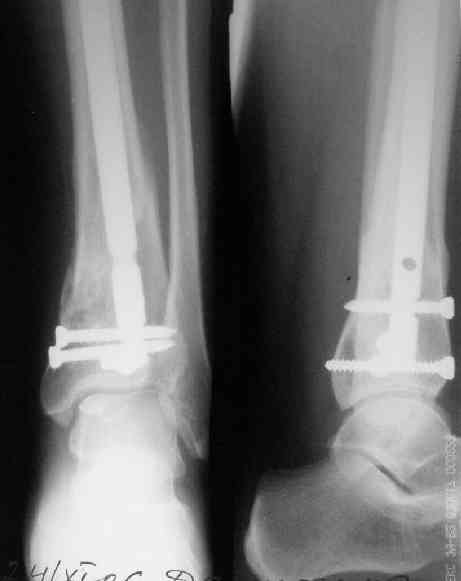

В приложении пример лечения аналогичного повреждения (плюс задний край).

Выполнил MIPO предизогнутой метафизарной LCP

Красиво получилось, поздравляю. Насчет немедленной полной нагрузки, как на гвозде, про что Алексей Семенистый говорит - будете разрешать сразу?

Подход индивидуальный, учитывая массу больного около 130кг, разрешу частичную нагрузку 15-20кг, через 4нед. Rg-контроль, при отсутствии признаков нестабильности полная нагрузка

И все же немного критики:1) Вы добивались анатомичной репозиции, которая требует абсолютной стабильности, которая в свою очередь возможноа только в условиях межфрагментарной компрессии. Пластина уложена как мостовидная, не хватает стягивающнго винта. 2) есть укорочение малоберцовой кости, необхордимо восстановить ее длину! В таком виде я бы не стал разрешать раннюю нагрузку. Добавить самую малость: стягивающий винт и остеосинтез малоберцовой кости и больной может наступать сразу.